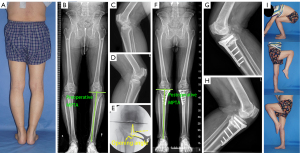

The study was conducted in accordance with the Declaration of Helsinki (as revised in 2013). The study was approved by ethics board of Shanghai Jiao Tong University affiliated Sixth People’s Hospital (No. 2020-107), and informed consent was taken from all the patients. To identify the preliminary relationship between hinge positions and the magnitude of the opening gap, the data of patients with knee osteoarthritis (OA), genu varum, and intra-articular incongruency treated by TCVO at our institute from January 2015 to December 2021 were retrospectively reviewed. To be eligible for inclusion in this study, patients had to meet the following inclusion criteria: have symptomatic medial unicompartmental knee OA with varus malalignment (a femoral tibial angle over 182°), an intra-articular deformity (a “pagoda-type” tibial plateau, lateral joint dilation with a joint line convergence angle over 5°, and increased medial tibial plateau depression less than −4°), a range of flexion >90°, a flexion contracture <10°, and a near-normal lateral femorotibial compartment [defined in accordance with the magnetic resonance imaging for articular cartilage examination, the radiographic assessment for joint features, and a Kellgren-Lawrence (K-L) grade <2]. Patients were excluded from the study if they met any of the following exclusion criteria: had rheumatoid or inflammatory arthritis, advanced patellofemoral arthritis, or lateral unicompartmental knee OA (diagnosed by radiographic evidence and clinical manifestation); and were smokers. A total of 66 patients with OA knees were included in the study and divided into group M (comprising 16 knees with the hinge points selected medial to the center of the intercondylar eminence), group C (comprising 21 knees with the hinge points selected at the center of the intercondylar eminence), and group L (comprising 29 knees with the hinge points selected lateral to the center of the intercondylar eminence). The number of TCVO cases at our institute during the study period determined the sample size of the study. The K-L grading system was used to assess the grade of OA based on the evaluation of a standing posteroanterior radiograph (16). The demographic characteristics of the patients are set out in Table 1.

Anteroposterior long-leg weight-bearing radiographs were collected to measure and compare the correction amount of MPTA (ΔMPTA) between the 3 groups. MPTA was defined as the angle formed between the tibial mechanical axis and the joint surface of the proximal tibia. The percentage of mechanical axis (%MA) was defined as the point at which the tibial plateau intersects the mechanical axis, converted to a percentage from the medial edge (0%) to the lateral edge (100%) of the tibial plateau. For each case, the ideal postoperative MPTA (po-MPTA) aimed to achieve a weight-bearing line with 60% %MA.

The demographic characteristics did not differ significantly among the 3 groups (Table 1). The inter- and intrarater reliabilities were satisfactory for the parameters, including the ΔMPTA (0.96 and 0.97) and the opening angle (0.96 and 0.97). No significant difference was observed in terms of the average ΔMPTA among the 3 groups (9.4±2.9°, 9.4±3.5°, and 9.3±3.0° for groups L, C, and M, respectively). The opening angle of the osteotomy gap differed significantly among the 3 groups (P<0.01), with the largest value in group M (29.7±11.1°) and the smallest value in group L (16.9±5.3°). A comparison of the opening angles per the ΔMPTA revealed a similar pattern, with significant differences across the 3 groups (P<0.01; Table 2).